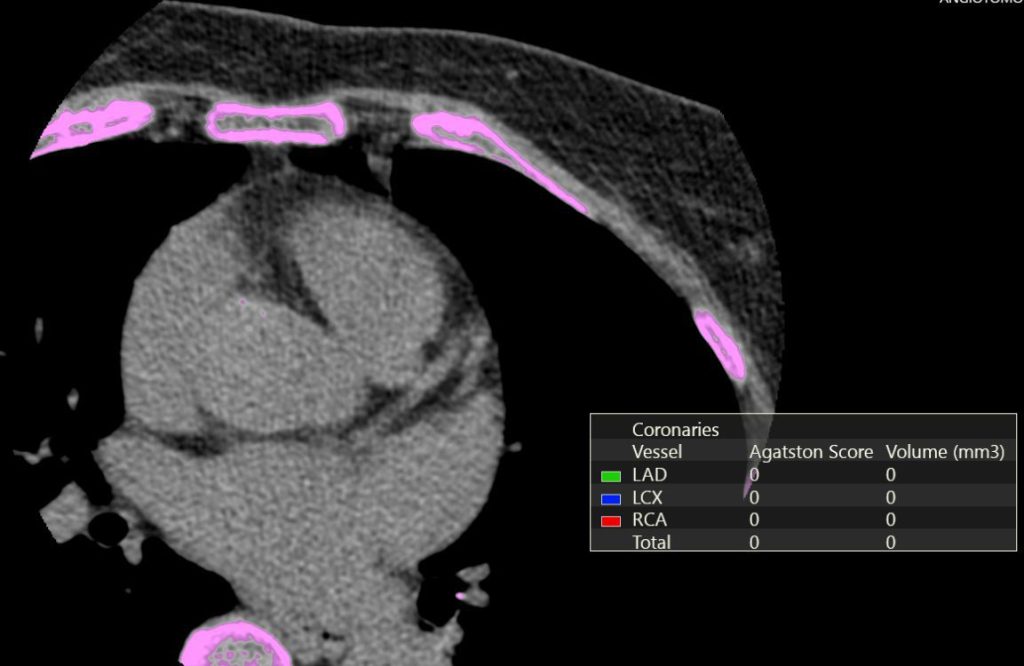

Atenção! Escore de cálcio exclusivo para estratificação de risco cardiovascular.

AngioTC de coronária: uma forma de personalizar e acompanhar o tratamento da aterosclerose

Como médico que realiza angioTC de coronária há mais de duas décadas, entendo que o maior valor do método não está apenas em identificar estenose significativa. O verdadeiro ganho clínico da angiotomografia coronária é permitir que o médico deixe de trabalhar exclusivamente com probabilidade estatística e passe a visualizar a doença aterosclerótica de forma concreta, individualizada e biologicamente coerente.